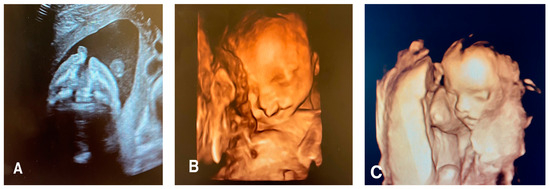

Micrognathia indicates a small chin secondary to underdevelopment of the mandible, while retrognathia means as abnormal posterior placement of the mandible (Figure 2).

Figure 2.

(A) A 2D coronal scan of the postnasal triangle of a 12 week old fetus where absence of the regular gap (see arrow) within the mandible indicates micrognathia and/or retrognathia. (B) Axial scan of the same fetus where the arrow indicating underdevelopment and/or posterior displacement of the chin (micrognathia and/or retrognathia). (C) Axial scan of the same fetus of 18 weeks with an inferior facial angle (IFA) (blue lines) of 45 degrees, diagnostic of micrognathia and/or retrognathia.

These two findings pose challenges in differentiation and can manifest concurrently. Micrognathia is frequently linked to syndromes or other abnormalities. Notable syndromes associated with micrognathia/retrognathia include Treacher Collins, Pierre Robin sequence, Stickler, and 22q11.2 deletion syndrome. Ultrasound imaging plays a crucial role, particularly the mid-sagittal profile, which helps evaluate the abnormal jaw position.

Numerous quantitative methods are considered for diagnosing micrognathia, utilizing both 2D and 3D ultrasound. Rotten et al. defined two-dimensional and three-dimensional sonographic parameters to objectively diagnose retrognathia and micrognathia between 18 and 28 weeks of gestation. Their findings indicated that retrognathia is associated with a decrease in the inferior facial angle (IFA). Therefore, a diagnosis of micrognathia/retrognathia can be established when the IFA measures less than 49.2°. This angle is defined by an orthogonal line to the vertical section of the forehead at the level of the nasal bone synostoses and a line connecting the chin’s tip to the anterior limit of the protrusive margin [30]. Despite these developments, diagnosing micrognathia/retrognathia remains challenging during both the second and the first trimesters. To address this, Sepulveda et al. proposed using ultrasound scans in the coronal view of the retronasal triangle to assess the midface during the first trimester. Their study revealed that a normal fetus exhibits a gap between the two mandibular bones, referred to as the mandibular gap. In contrast, fetuses with micrognathia/retrognathia lack this gap, or the mandible cannot be identified at this level. However, further research is necessary to determine the sensitivity and specificity of the first-trimester retronasal triangle view to detect cleft palate. Consequently, an early-second-trimester targeted scan remains a complementary diagnostic examination to consider [31].